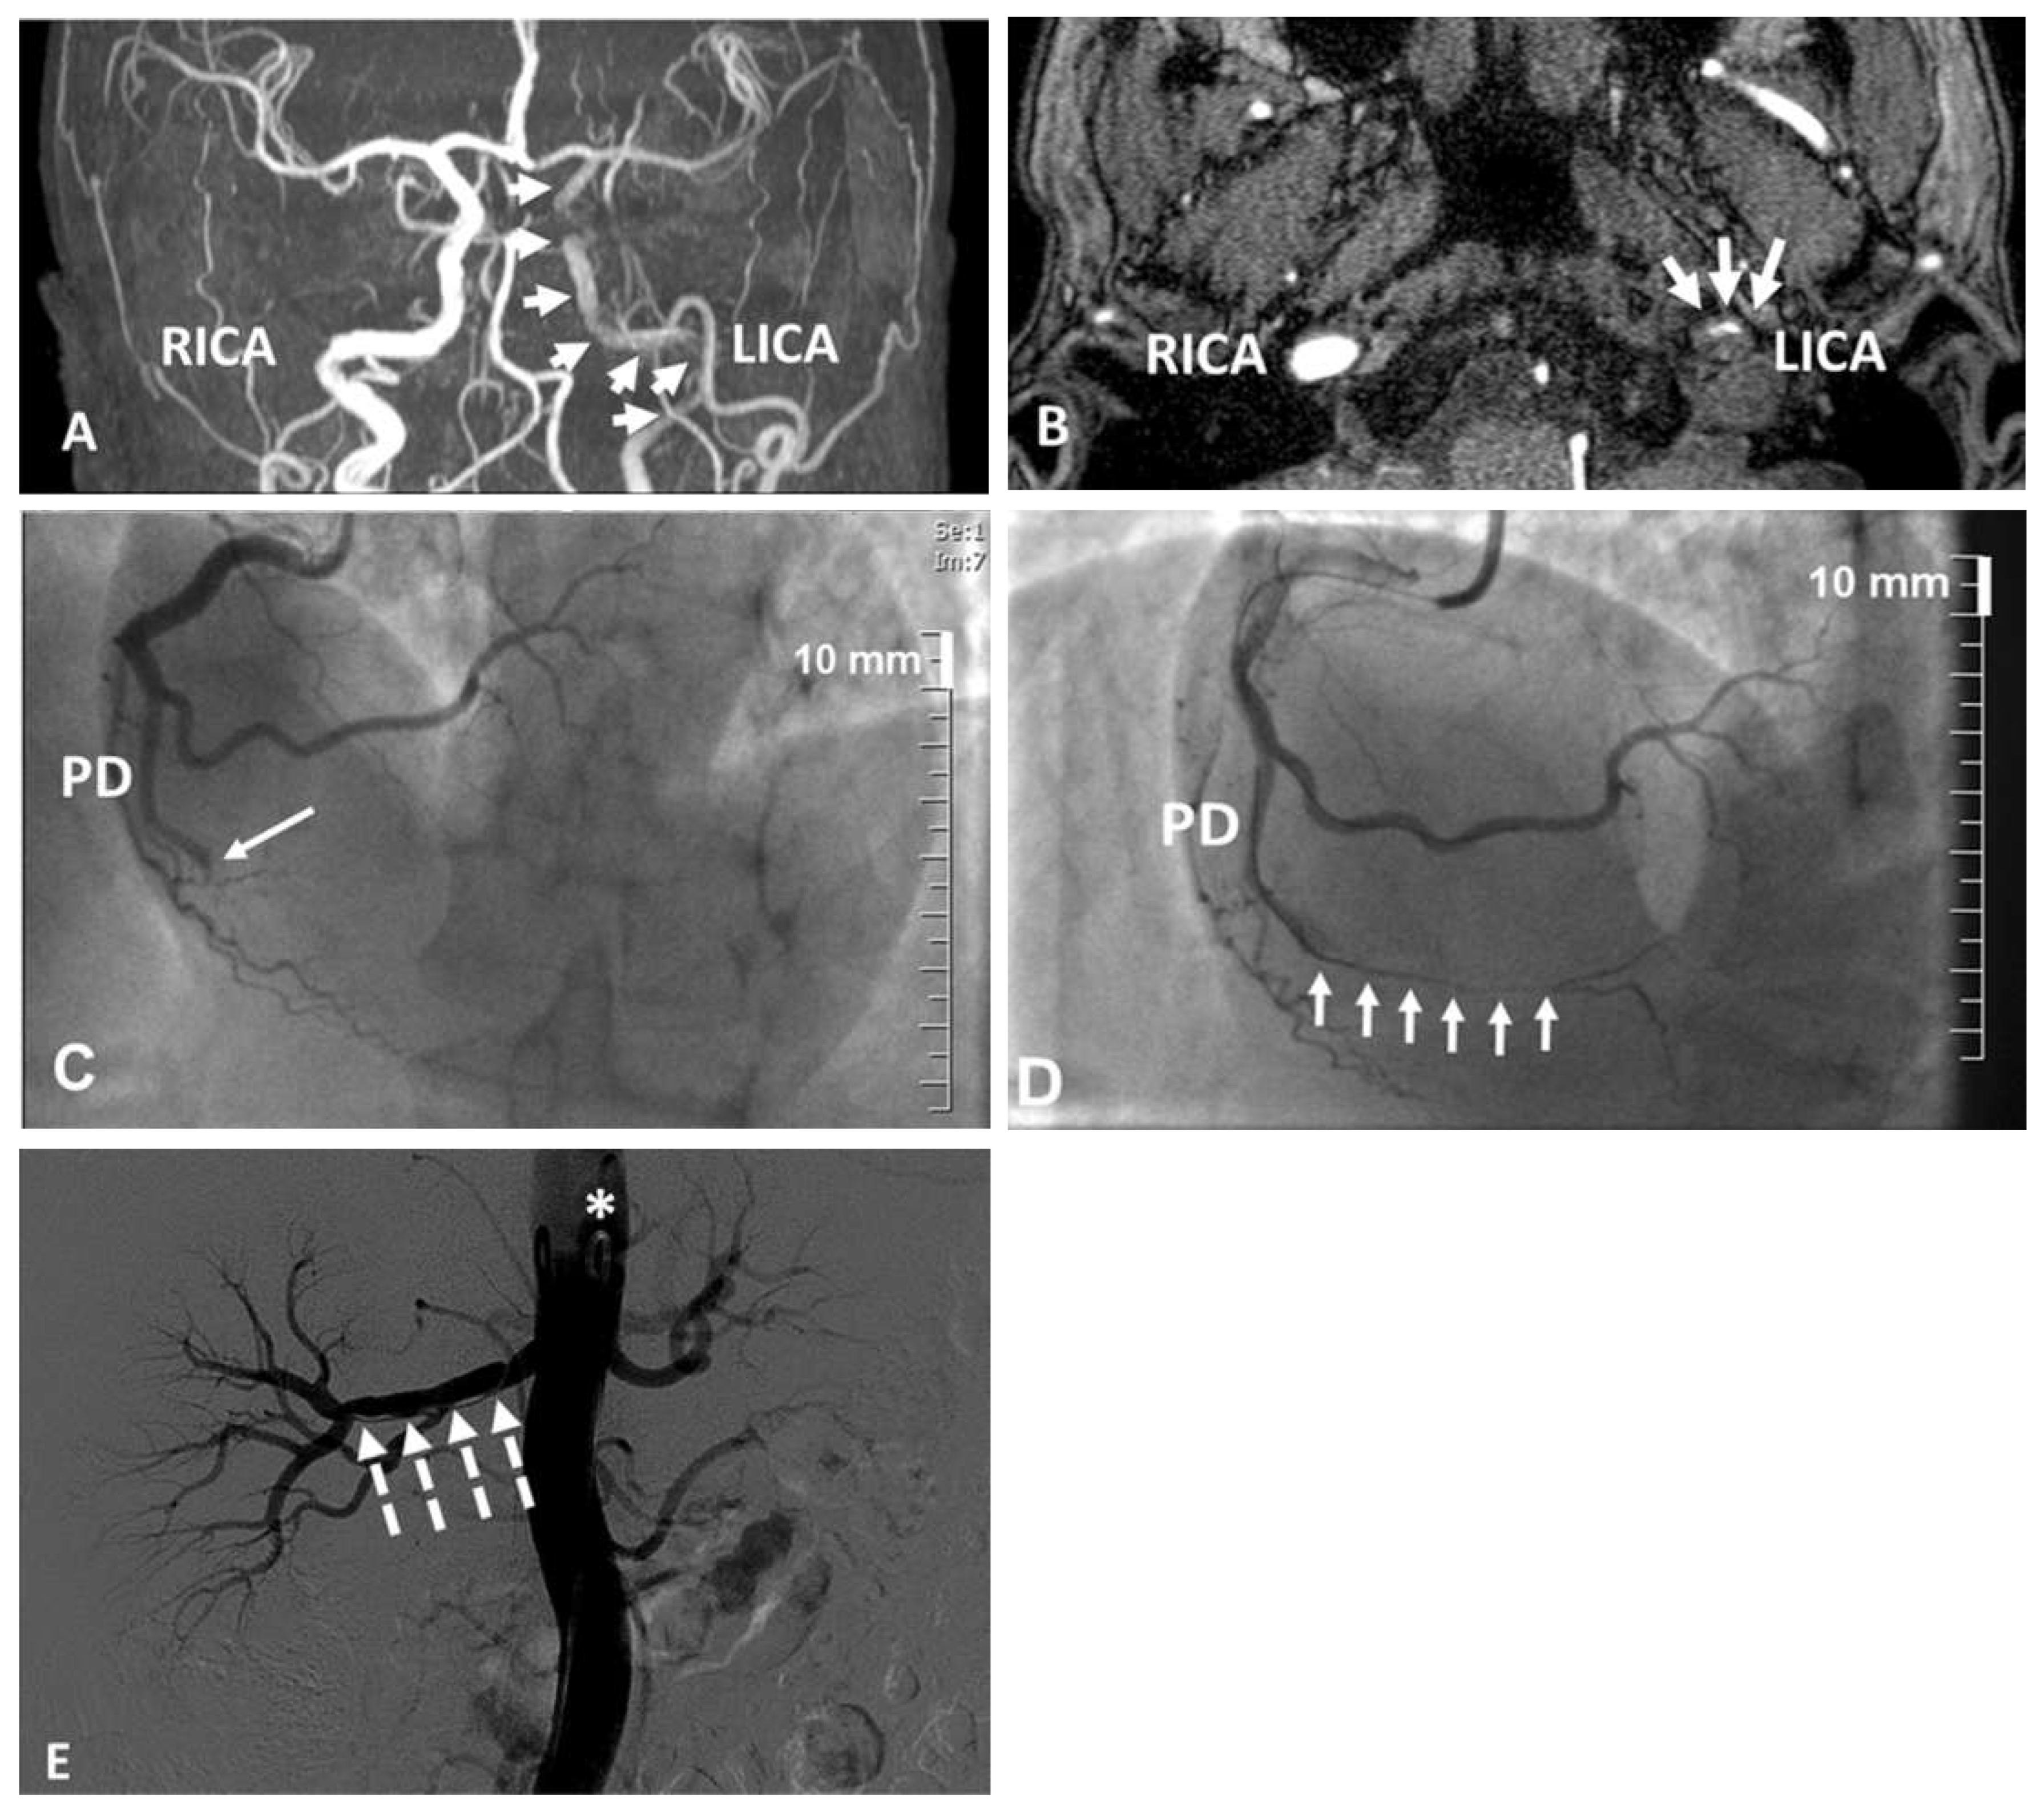

A 45-year-old woman was admitted to our stroke unit because of acute right hemiparesis, aphasia and moderate frontal headache while running on a treadmill. She had no cardiovascular risk factors apart from previous smoking. Furthermore, no recent infections, blunt neck trauma, medical or surgical procedures or risk factors for bleeding were identified. Brain multidetector computed tomography (MDCT) showed neither acute ischaemic nor haemorrhagic lesions, while MDCT angiography and magnetic resonance imaging angiography (MRA) revealed a 1-cm long sub-occlusive dissection of the left internal carotid artery (LICA) at the level of the cervical-petrous segment junction (Figure 1A–B). Aortic MDCT angiography excluded the presence of Stanford type A aortic dissection. Treatment with aspirin and neurological follow-up were implemented for the LICA spontaneous dissection [1]. Ten days later the patient was admitted because of acute chest pain at rest later diagnosed as ST-segment elevation acute myocardial infarction. Primary selective angiography of the right coronary artery, via the radial approach, disclosed distal posterior descending artery (PD) occlusion (Figure 1C; online-only Data Supplement Video 1). The lesion was carefully crossed with a guidewire, revealing a subocclusive stenosis along the entire distal PD (Figure 1D; online-only Data Supplement Video 2). On the basis of the characteristics of the lesion and the absence of any additional coronary atheromatosis, the diagnosis of spontaneous coronary artery dissection was retained [2]. Due to the small diameter of the vessel lumen, no intravascular imaging was performed and a conservative approach was chosen.

Four days later, the patient reported acute right back pain. Abdominal aorta MDCT angiography revealed spontaneous right renal artery dissection. It was confirmed by nonselective renal artery angiography, which also suggested fibromuscular dysplasia (FMD) because of the presence of a possible “string of beads” lesion, but only in a side branch of the renal artery (Figure 1E). A conservative approach was preferred [2,3]. Since the arterial lesion was not pathognomonic for FMD, genetic testing for vascular Ehlers-Danlos syndrome (COL3A1 mutation) was also performed, but the results were negative.

Figure 1. (A–B) Magnetic resonance (MR) angiography displaying subocclusive dissection of the left internal carotid artery. (A) Frontal plane reconstructed MR angiography of the dissected LICA: hypoperfusion is evident distally to the dissection (arrows). (B) Coronal plane MR angiography of the dissected LICA (dotted arrows) showing the almost occluded true lumen of the LICA (dotted arrows). LICA = left internal carotid artery; RICA = right internal carotid artery. (C–D) Selective coronary angiography of the right coronary artery disclosing possible posterior descending artery dissection. (C) Diagnostic injection demonstrating complete distal PD occlusion (big arrow). (See online-only Data Supplement Video 1.) (D) Severe and diffuse lumen narrowing (arrows) of the entire small PD after crossing the occlusion by the guidewire (*). (See online-only Data Supplement Video 2.) PD = posterior descending artery; PL = posterolateral artery. (See online-only Data Supplement Video 1.) (E) Nonselective right renal artery (RRA) angiography. It displays long dissection of the right renal artery (big dotted arrows) and indicates possible side-branch “string of beads” lesions (arrows). 4 F pigtail catheter used for non-selective RRA angiography (*).